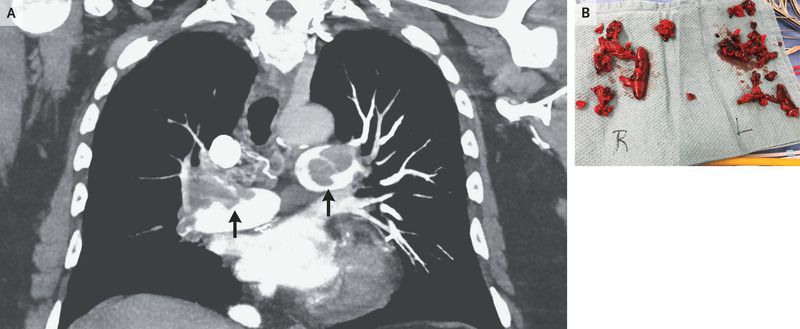

A 64-year-old man presented to the emergency department with a 2-week history of worsening shortness of breath. He had been in good health previously and had not undergone recent surgeries or had periods of prolonged immobilization. The oxygen saturation was 84% while he was breathing ambient air, and the blood pressure was 156/103 mm Hg. A physical examination was notable for swelling of the right calf. An electrocardiogram showed extreme right-axis deviation and T-wave inversions in the lateral leads. Computed tomography of the chest showed thrombus in both the right and left pulmonary arteries (Panel A, arrows), as well as a linear density in the right ventricle. Transthoracic echocardiography confirmed the presence of a 6-cm thrombus in the right ventricle Duplex ultrasonography showed extensive deep venous thrombosis in the right leg. The patient underwent surgical thrombectomy, which resulted in reduction of an extensive clot burden (Panel B). He did well postoperatively and was treated with apixaban. At a follow-up visit 1 month after surgery, his oxygen saturation was 94% while he was breathing ambient air, and he had improving exercise capacity.